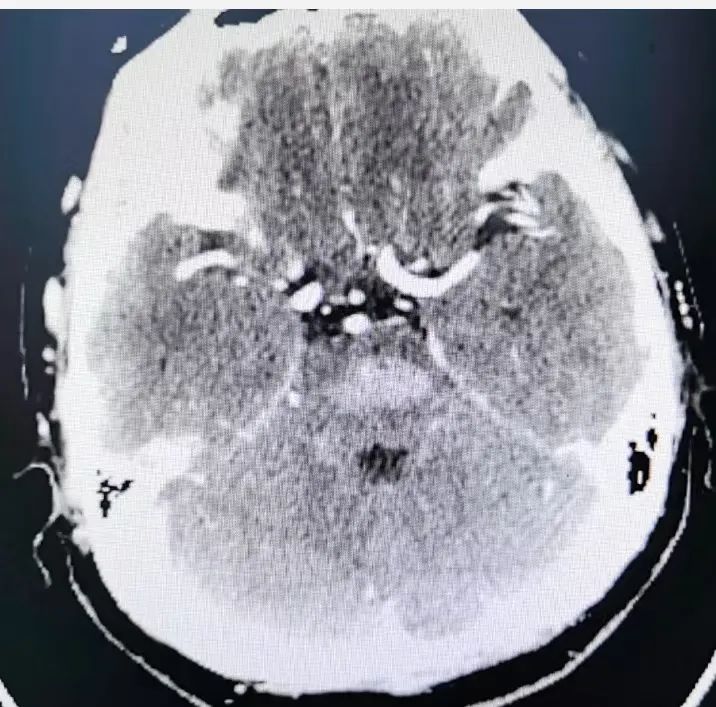

近日,北京朝阳医院神经外科副主任医师谭可带领团队成功挽救了一名重症桥脑中脑出血患者。这位54岁的女性患者因突发意识不清一小时而被紧急送往朝阳医院急诊。患者既往有高血压病史,但未规律服药控制。送达医院时,患者已处于深度昏迷状态,GCS评分3分,双侧瞳孔呈针尖样,急诊一站式卒中CT检查显示桥脑中脑存在大面积出血。在充分了解手术风险后,患者家属签字同意并积极要求手术治疗。

术前CT显示患者大面积脑干出血